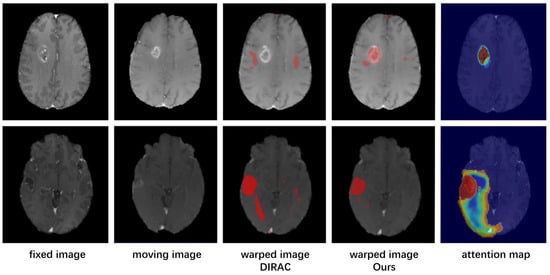

- To further eliminate adverse effects of possible registration biases, our model incorporates a corrected attention module that enhances the model’s focus on areas with significant deformation and integrates the clinical data of the area if that certain pathological area of the preoperative image should have no corresponding relationship.

2.4. Corrected Attention Module

3.4.2. Results and Analysis